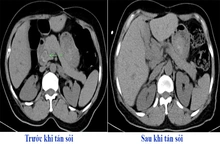

baophutho.vn Vừa qua, Đơn vị Phẫu thuật tim mạch và lồng ngực - Bệnh viện Đa khoa tỉnh phẫu thuật thành công trường hợp suy tim giai đoạn 4 do hở van hai lá...